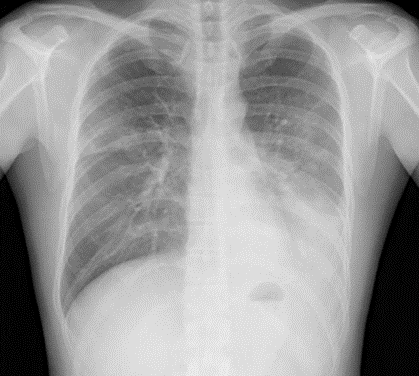

肺炎と考えたが浸潤性粘液産生腺癌だったレントゲン(X-p)写真

この写真を見たら何を考えるでしょうか?

所見としては、心陰影はシルエットサイン陰性、下降大動脈はシルエットサインは陽性、左横隔膜はシルエットサインは陽性です。

胃泡の位置(横隔膜下数cm)が確認できることより左横隔膜は下がっていないことも推測できます。

この写真を見たらまず肺炎を考えます。(シルエットサインから推測すると下葉ということになる)

その後の臨床経過とすると、抗生剤加療で浸潤影良くならず、気管支鏡検査施行し、浸潤性粘液産生腺癌と診断されました。